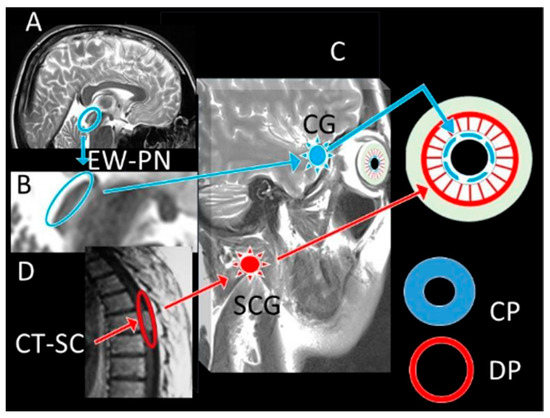

The normal and degenerated neuron densities within the Edinger–Westphal nucleus were subsequently quantified using stereological methods. Furthermore, degenerated neuron densities of the Edinger–Westphal nucleus (n/mm3), pupil diameters (micrometres), and pupil index values (PIV) were compared between the groups (Figure 1, Figure 2 and Figure 3). The pupil index value, referred to as the DADA index, was defined as the ratio of the iris surface area to the pupil surface area and calculated using the formula: PIV(DADA-I) = (IRr2 − Pr2)/Pr2 (where IR represents the radius of the iris and Pr represents the radius of the pupil). This formula is visually represented in Figure 1.

Figure 1.

Pupil Measurements and DADA Index Schematic: (A) Optical Coherence Tomography (OCT) measurement of a dilated pupil (DP). (B) OCT measurement of an isocoric pupil (IP). (C) OCT measurement of a contracted pupil (CP). (D) Schematic diagram illustrating the components of the DADA Index (DADA-I) calculation, defined as the ratio of the iris surface area (IRr2) to the pupil surface area (Pr2). The diagram shows the radii for a dilated (DPr), isocoric (IPr), and contracted (CPr) pupil relative to the total iris (I). The formula is: DADA-I = (IRr2 − Pr2)/Pr2.